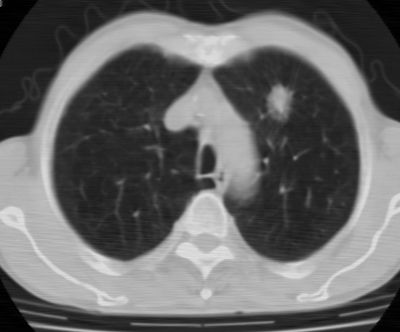

标题: CT24783:m71,既往肺心病史3年,现咳嗽,憋喘。 [打印本页]

标题: CT24783:m71,既往肺心病史3年,现咳嗽,憋喘。

1、左肺上叶spn,毛刺+分叶+血管集束征,考虑周围型肺癌可能性大

2、全小叶性肺气肿。

1)左肺上叶周围型肺癌可能。2)两肺全小叶型肺气肿。

左上周围型肺癌,全小叶型肺气肿。